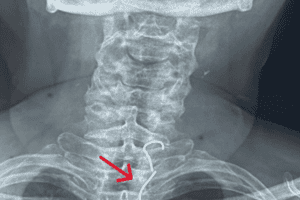

Bệnh nhân Kim Thị K. (61 tuổi) vào cấp cứu trong tình trạng không ăn uống được, nặng ngực, khó thở, mệt mỏi. Theo thông tin bệnh nhân cung cấp thì trước nhập viện 1 ngày, bệnh nhân nuốt phải răng giả hàm trên có 3 cây răng giả và móc kim loại. Sau đó, bác sĩ Khoa Tai Mũi Họng cho chụp X-quang cổ ngực thấy có dị vật cản quang bất thường, có hình móc câu ở 2 đầu, vị trí nằm ngang đốt sống ngực T1 - T2.

Hình chụp X-quang dị vật trong thực quản bệnh nhân